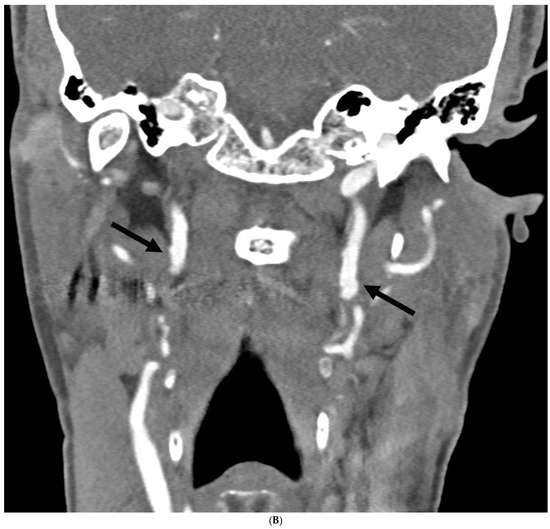

Prevalence of Intracranial and Cervical Artery Abnormalities in Patients with Hypermobile Ehlers–Danlos Syndrome and Hypermobility Spectrum Disorders Presenting to an Academic Headache Clinic

by Todd D. Rozen, Katelyn A. Bruno, Ethan M. Rozen, Frances C. Wilson, Marysia S. Tweet, Raymond C. Shields, Sharonne N. Hayes, Dacre R. T. Knight, Shilpa N. Gajarawala, Sukhwinder J. S. Sandhu, Alok A. Bhatt and DeLisa Fairweather

Neurol. Int. 2026, 18(2), 33; https://doi.org/10.3390/neurolint18020033 - 11 Feb 2026

Background/Objective: It remains unknown whether patients with the more common forms of hypermobility carry an elevated risk for the development of intracranial/cervical artery abnormalities. The objective of this study was to determine the prevalence of unruptured intracranial aneurysms, spontaneous cervical artery dissections, and fibromuscular dysplasia in patients with hypermobile Ehlers–Danlos Syndrome (hEDS) and hypermobility spectrum disorders (HSD) who presented to an academic headache clinic. Methods: This is a retrospective cohort study. We used an electronic medical record to look for all patients seen at the Mayo Clinic Florida Headache Center and EDS Clinic between 2019 and 2025 with a diagnosis of hEDS or HSD and neuroimaging of both the intracranial and cervical arteries. Results: There were 103 patients who met the inclusion criteria. There was no statistically significant difference between hEDS and HSD patients in developing cerebral/cervical arterial anomalies. Of the sample, 95% of the hypermobile patients with abnormal neuroimaging also had migraine. A total of eleven (10.7%) patients (hEDS + HSD) were diagnosed with unruptured intracranial aneurysms. Trends included age less than 50 years, small aneurysms in the anterior circulation, and having migraine with aura. Five (4.8%) patients were diagnosed with spontaneous cervical artery dissection with trends for HSD, over the age of 50 years, vertebral artery involvement and a history of migraine without aura. Six (5.8%) patients were diagnosed with fibromuscular dysplasia with trends for HSD, over the age of 50 years, carotid artery involvement and a history of migraine with aura. Conclusions: This is the first study to identify that patients with the more common type of EDS, HSD and hEDS, and a possible concomitant history of migraine have a heightened risk for the development of unruptured intracranial aneurysms, spontaneous cervical artery dissections, and fibromuscular dysplasia. Our findings suggest the need for targeted screening with intracranial and extracranial arterial imaging for this unique patient population. Full article